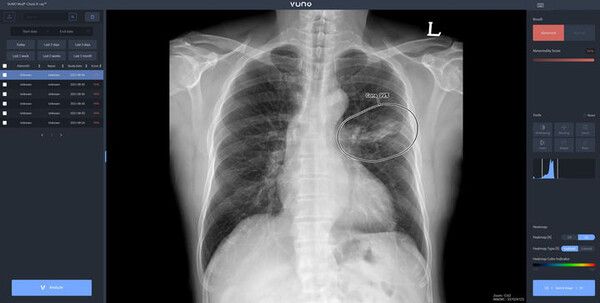

뉴시스 보도에 따르면, 26일 의료계에 따르면 기흉은 폐에 생긴 구멍으로 공기가 새면서 폐 밖(흉막강) 안에 공기가 차는 질환이다.

기흉은 자발성 기흉과 외상성 기흉으로 구분된다. 자발성은 일차성 기흉과 이차성 기흉으로 나뉜다. 일차성 기흉은 건강한 사람에게 발생하며, 폐의 가장 윗부분 흉막에 있는 작은 공기주머니에 의해 발생한다. 일차성 기흉의 원인은 분명하지 않지만 환자의 대부분이 키가 크고 말랐거나 흡연자라는 보고도 있다. 이차성 기흉은 폐질환을 앓고 있던 사람에게 발생한다. 여기에는 결핵, 악성 종양, 폐섬유증, 만성 폐쇄성 폐질환, 폐기종 등이 있다.